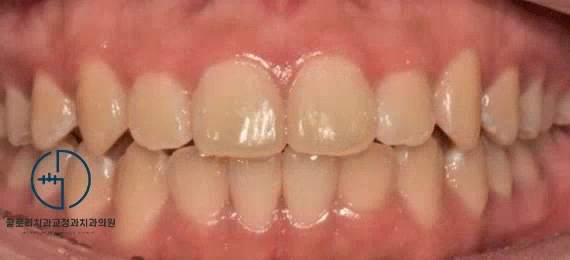

환자의 초진 사진을 살펴보면

한눈에 봐도 윗니가 아랫니를 꽤 많이

덮고 있는 것을 볼 수 있습니다.

과개교합이 나타난 것으로 확인이 되는데요.

이는 쉽게 말해 정상에 비해 아랫니가 잘 보이지 않는 것을 뜻합니다.

이와 더불어 삐뚤어진 치열도 눈에 띕니다.

전체적으로 총생(crowding)이 나타난 것을 확인할 수 있었습니다.

이전과는 달리 눈에 띄게 달라진 피개량이 관찰됩니다.

다행히 정상적인 교합량을 갖게 되었으며

정중선도 알맞게 개선된 것을 확인할 수 있네요.

구치 배열도 1치대 2치 관계로 이상적인 맞물림을 갖게 되었으며

악궁의 형태도 전에 비해 더 둥근 U자 모양으로 바뀌었습니다.